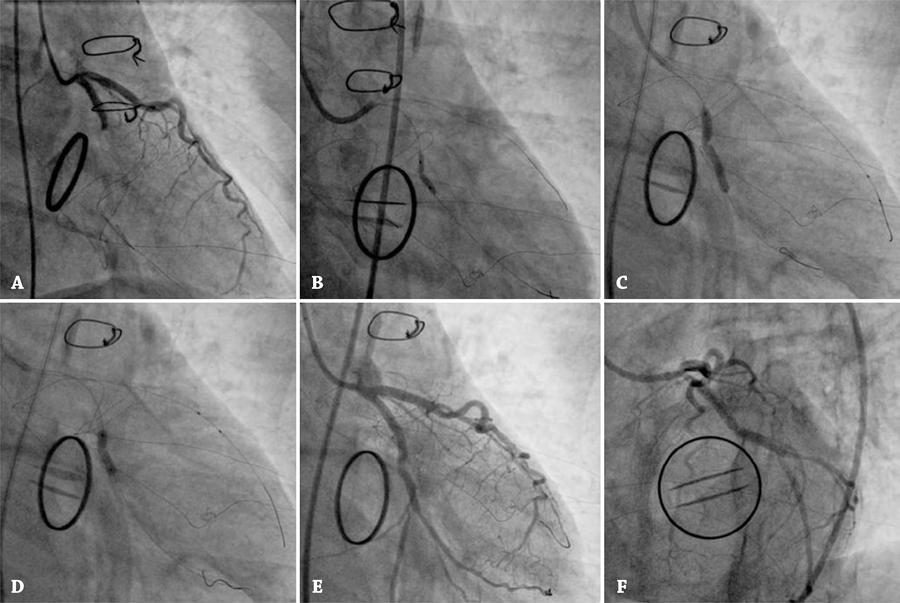

Figura 3

Cineangiocoronariografia no pós-operatório imediato. (A) Oclusão da coronária circunflexa. (B) Pré-dilatação da estenose coronariana com balão não complacente. (C) Implante de stent convencional, ilustrando a formação de “cintura” no balão-guia. (D) Pós-dilatação do stent com balão não complacente. (E e F) Resultado angiográfico.